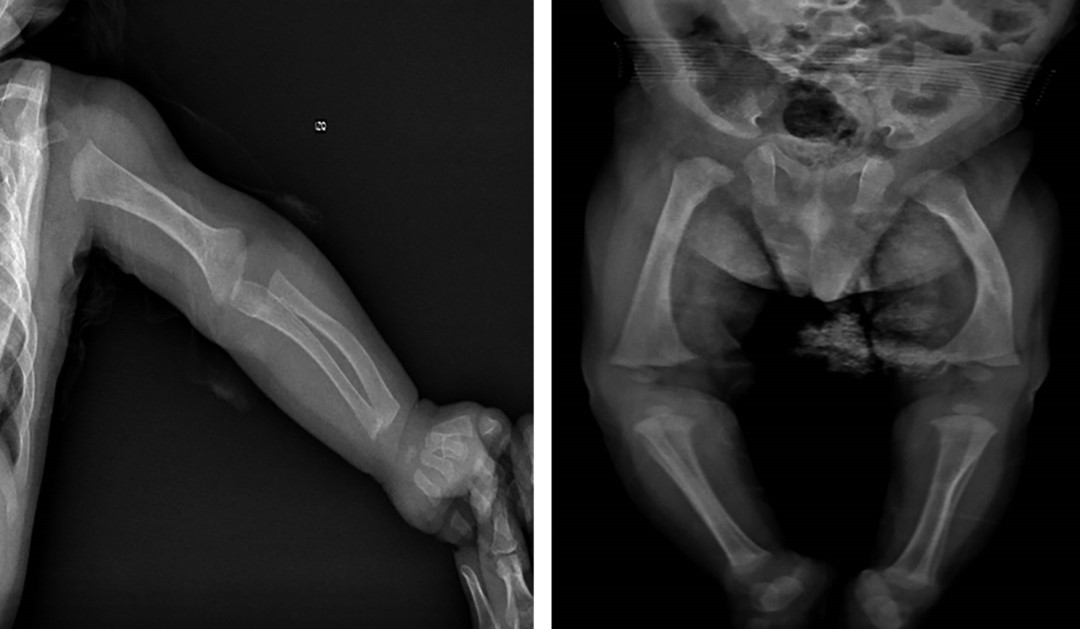

A los 62 días de vida presenta episodio de deterioro respiratorio, por lo que se realiza radiografía toracoabdominal en la que se evidencia disminución de la densidad radiológica ósea con presencia de signos de desmineralización, en particular deshilachamiento de metáfisis de húmero (Figura 1). Al tomar otras radiografías de las extremidades se evidenciaron múltiples fracturas de huesos largos, con signos de pérdida de línea metafisaria, desmineralización, deshilachamiento, imágenes en cáliz de copa (Figura 1).

Dados los hallazgos radiográficos, es valorado por ortopedia y endocrinología pediátrica, quienes consideran que el cuadro corresponde a EMOP, con relación calcio/fósforo 3:1. Se recomienda disminuir los factores de riesgo asociados a la desmineralización, ajustando manejo de vitamina D a 1,000 UI. El paciente evolucionó satisfactoriamente logrando egreso a los 89 días de vida.